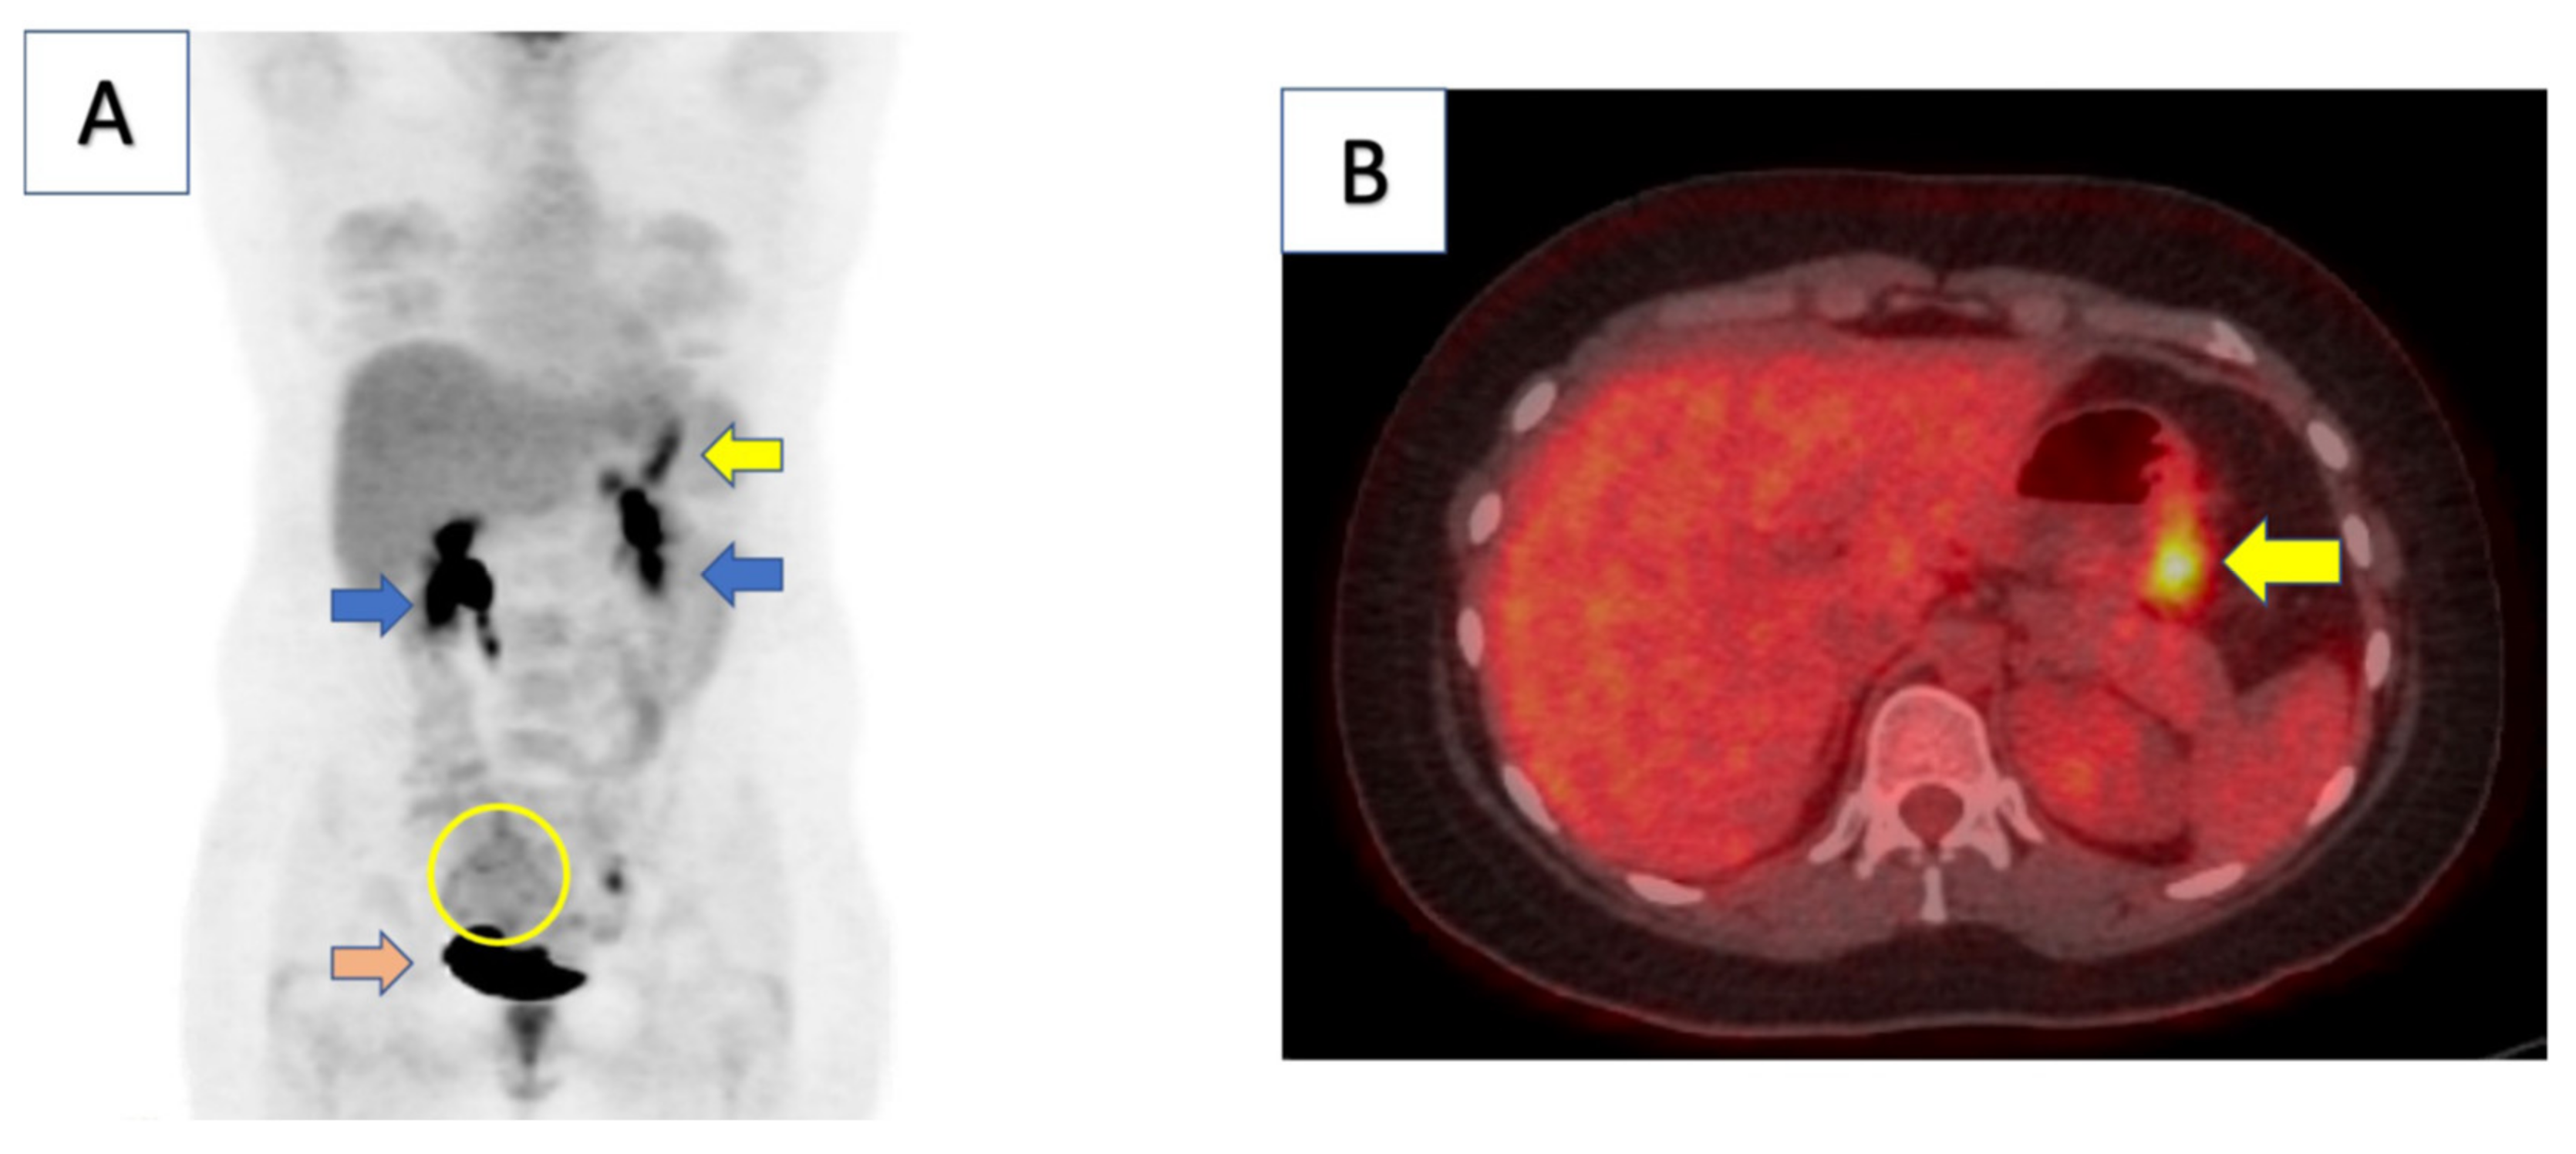

2. Case Report

2.1. Clinical Course